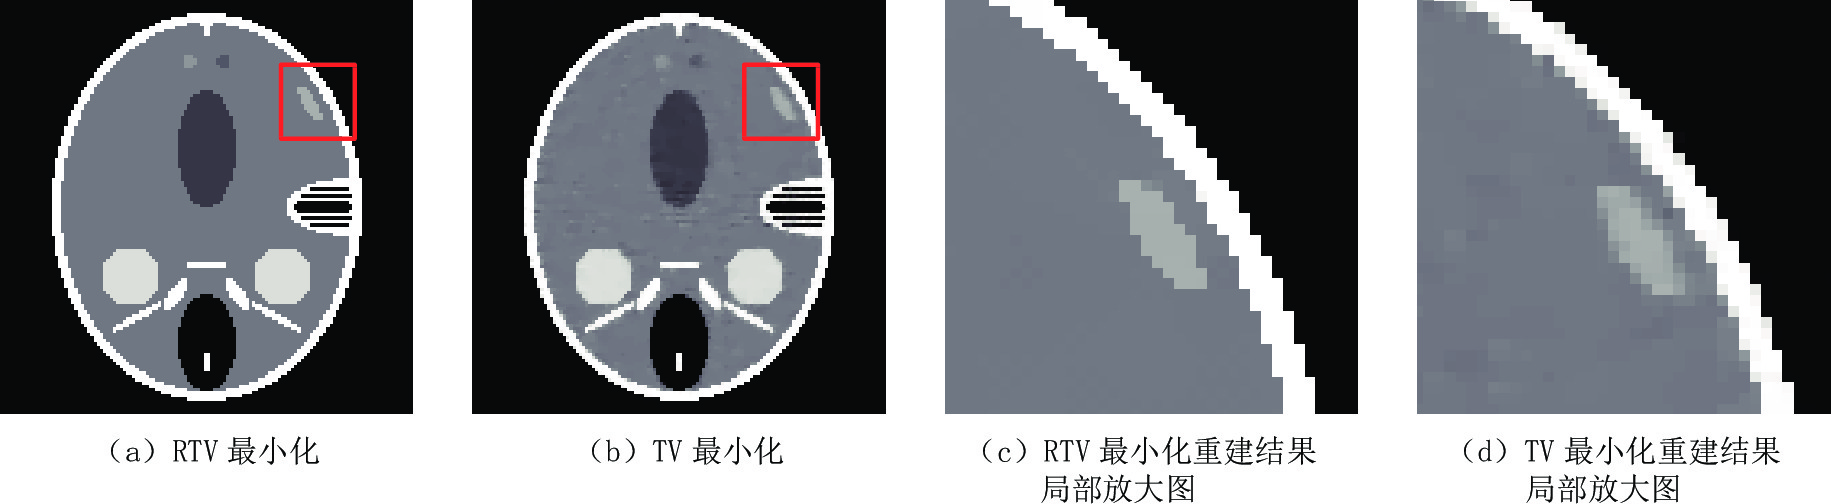

选择FORBILD模体在50个投影角度,并于投影数据中加入方差为0.05的高斯白噪声条件下的重建结果进行阐述。如图10所示,图10(a)是RTV算法的重建结果,图10(b)是TV最小化重建结果,图10(c)和图10(d)分为各自重建结果的局部区域放大图。可见,TV模型和RTV最小化重建模型都显示出了对噪声的抑制特性。但是,通过对比可见,RTV最小化模型重建结果的图像结构明显有着更清晰的边缘间隔,并且从整体看,RTV最小化模型的重建结果更加锐利清晰。